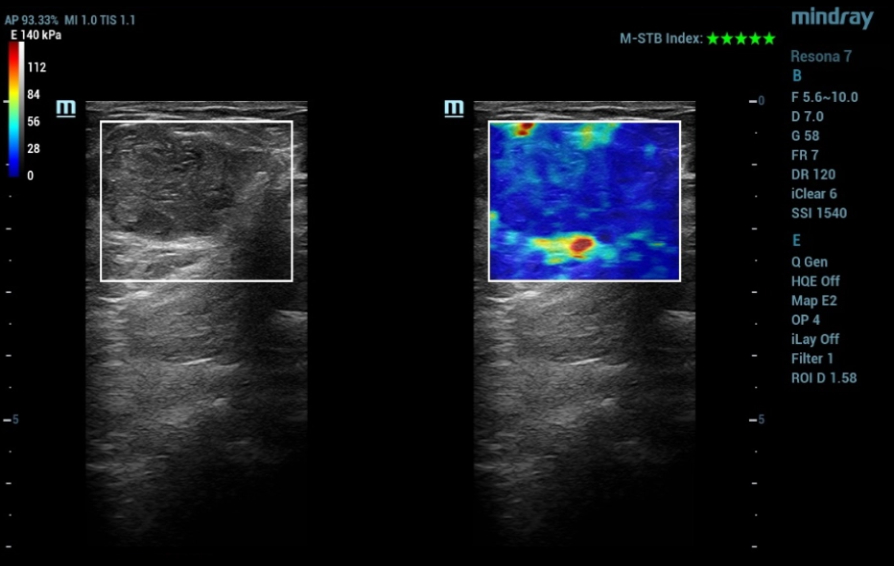

Mindray commenced its first #Nuewa Club Meeting in Bucharest, Romania!

Bajo el tema ŌĆ£inspirando el cuidado de la salud de la mujerŌĆØ, se llev├│ a cabo en la Ciudad de Panam├Ī la primera conferencia de Nuewa Club en Latino America.?